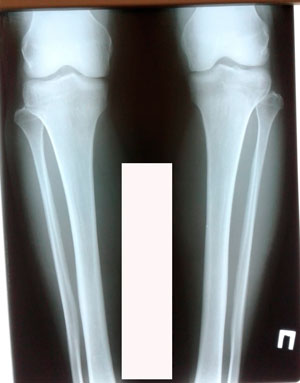

Исходник - 35 лет.

Дата операции - 21.01.2020

IMG_8372-20-01-20-04-59.JPG

IMG_8374-20-01-20-04-59.JPG